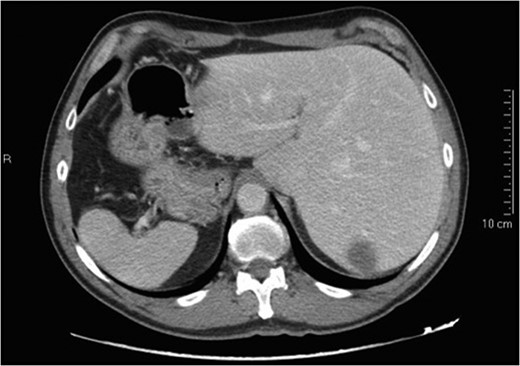

Situs inversus totalis (SIT) is a congenital condition consisting of a mirror image of transposition of the abdominal and thoracic organs occurring in about 1:5000 to 1:10 000 adults. We report on a 60-year-old male with a single colorectal liver metastasis in the Segment 7. The patients underwent a totally laparoscopic sub-segmentectomy. Intraoperative approach on a reverse posterior segment was difficult because of left-sided position of the liver. Postoperative course was uneventful and the patient was discharged after 5 days. To our knowledge, only a few cases of open liver resections in patients with SIT have been published. This is, therefore, the first case of laparoscopic liver resection for colorectal liver metastasis in a patient with SIT. We provide the readers with useful tips to perform minimally invasive liver surgery in such patients.

Situs inversus is a congenital condition with an incidence ranging between 1:1000 and 1:10 000 characterized by left-to-right transposition of one or more normally asymmetrical organs of the body. Situs inversus totalis (SIT) consists of a mirror-image transposition of the abdominal and thoracic viscera, which occurs in about 1:5000 to 1:10 000 adults [1]. Patients affected by SIT are usually completely asymptomatic, but they have more commonly major defects which can shorten their lifespan [1].

We herein present the case of a patient with a single colorectal liver metastasis with SIT providing the readers with useful information to approach this condition.